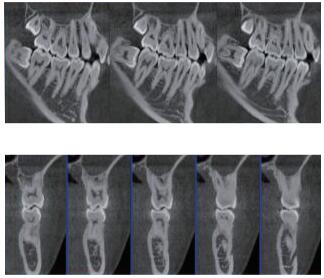

三維重建任意斷層

專有三維重建算法,可提供任意位置高清斷層影像。

多平面組合重建

可同時觀察軸向面、冠狀面和矢狀面圖像,方便臨床診斷。